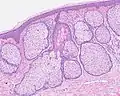

فرط التنسج الدهني[1] أو فرط التنسج الزهمي[1] (بالإنجليزية: Sebaceous hyperplasia) هو اضطراب في الغدد الدُهنية، حيثُ تتضخم، مما يؤدي إلى ظهورِ تحاديب سُرية الشكل لامعة صفراء أو لحمية اللون.[2] يتميز فرط التنسج الدهني غالبًا بانتفاخ العُقيدات المُتكونة حديثًا مع التعرق، ولكنها تتقلص مع مرور الوَقت.

غالبًا ما يؤثر فرط التنسج الدهني على حديثي الوِلادة واكبار السن في مُنتصف العمر. تظهر هذه الحالة على شكل حطاطات 1-5 ملم على الجلد، وغالبًا في جبهة الرأس والأنف والخدين والجلد الدهني في الوجه، وقد تكون على شكلِ القرنبيط. في الرُضع، يرتبط حب الشباب عادةً مع فرط التنسج الدهني.